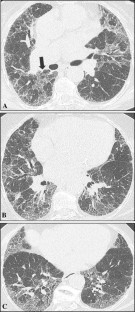

Fig. 2